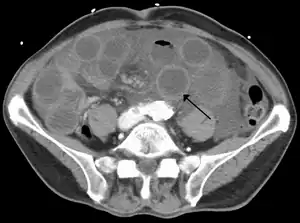

![]() Computer tomography (CT) showing ischemic small bowel due to thrombosis of the superior mesenteric vein. The small bowels are dilated and the bowel wall is thickened. | |